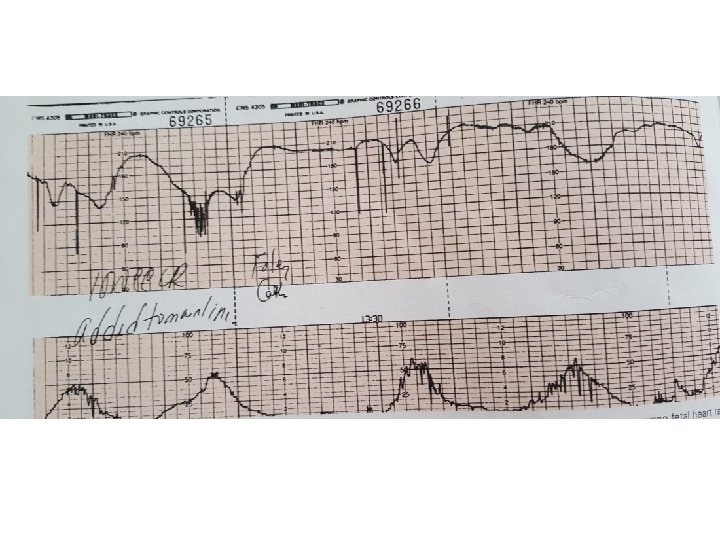

Confusing aspect • Late component • Combined pattern absent variability post blunted acceleration (overshoot) no acceleration

Variable Deceleration Typical: • shoulders Atypical : • Overshoot • Loss of primary shoulder • Slow return to baseline (late component) • Baseline returns to a lower level(after deceleration) • Biphasic(W shape) • loss of variability during deceleration

Complicated variable deceleration Indicated fetal hypoxia • Tachycardia • Lack of variability • Slow return to baseline • Large amplitude(to 60 bpm or duration 60 second) • Loss of pre and post shouldering • Smooth overshoot